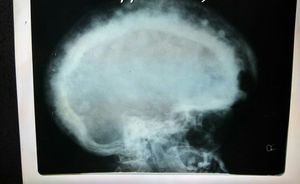

X-ray

Diagnosis?

Hydrocephalus

Thalassemia....hair on end appearance